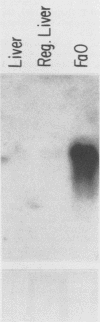

A basic phosphoprotein defined by a monoclonal antibody named AF5 was found to be highly abundant in human hepatocellular carcinoma by Western immunoblotting. Under the same conditions, the levels of this phosphoprotein were low or undetectable in normal liver extracts. The AF5 antibody was used to screen a cDNA expression library of a human hepatoma cell line named FOCUS. A 960-base-pair cDNA was isolated and found to be a partial cDNA encoding the human protein-tyrosine kinase substrate p36, also known as lipocortin II. p36 expression was highly abundant in hepatocellular carcinomas at both the transcript and protein levels. Its expression was not induced significantly during rat liver regeneration following a partial hepatectomy. These results suggest that the induction of p36 expression is associated with malignant transformation of hepatocytes. p36 was previously shown to be phosphorylated upon transformation of normal fibroblasts by retroviral oncogenes without significant modulation of expression. We report here the initial description of the association of increased p36 expression with malignant transformation.